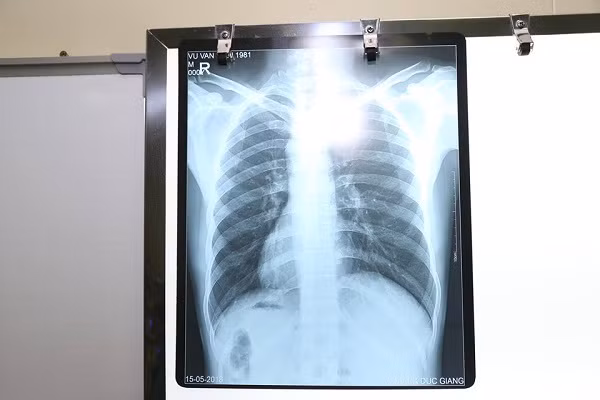

Kết quả chụp Xquang cho thấy bệnh nhân có phủ tạng nằm đảo ngược hoàn toàn so với bình thường

Sau khi thăm khám, xét nghiệm, siêu âm, chụp Xquang, các bác sĩ rất bất ngờ với hình ảnh trái tim cùng với các phủ tạng khác trong lồng ngực và bụng của bệnh nhân H. ở vị trí "soi gương" so với bình thường. Tức là, trái tim và dạ dày ở bên phải, còn gan và ruột thừa thì ở bên trái.